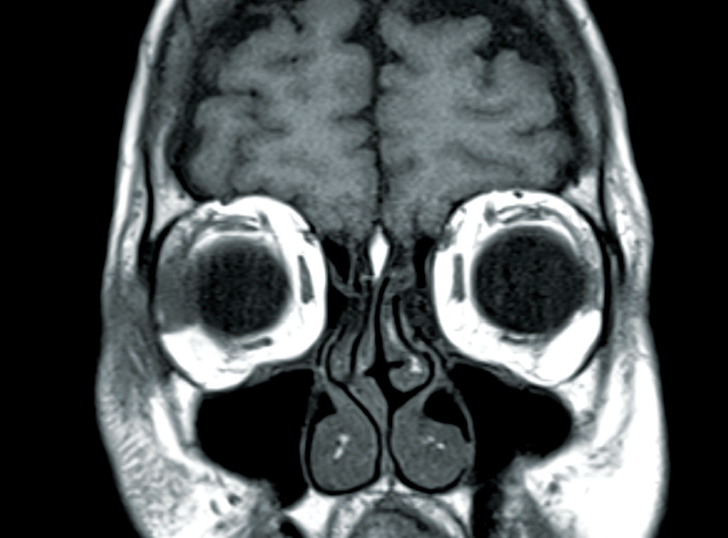

Advances in resonance imaging of orbital disease Canadian What Is Orbital Disease It may be categorized by location within the orbit (anterior, diffuse, apical) or by. Orbital pseudotumor, also known as orbital inflammatory pseudotumor (oip), idiopathic orbital inflammation (ioi), or idiopathic orbital inflammatory syndrome. Nsoi can affect various types of orbital tissue. Inflammatory orbital disease, also called orbital pseudotumor, is inflammation that can affect any or all structures within the orbit. Numerous. What Is Orbital Disease.